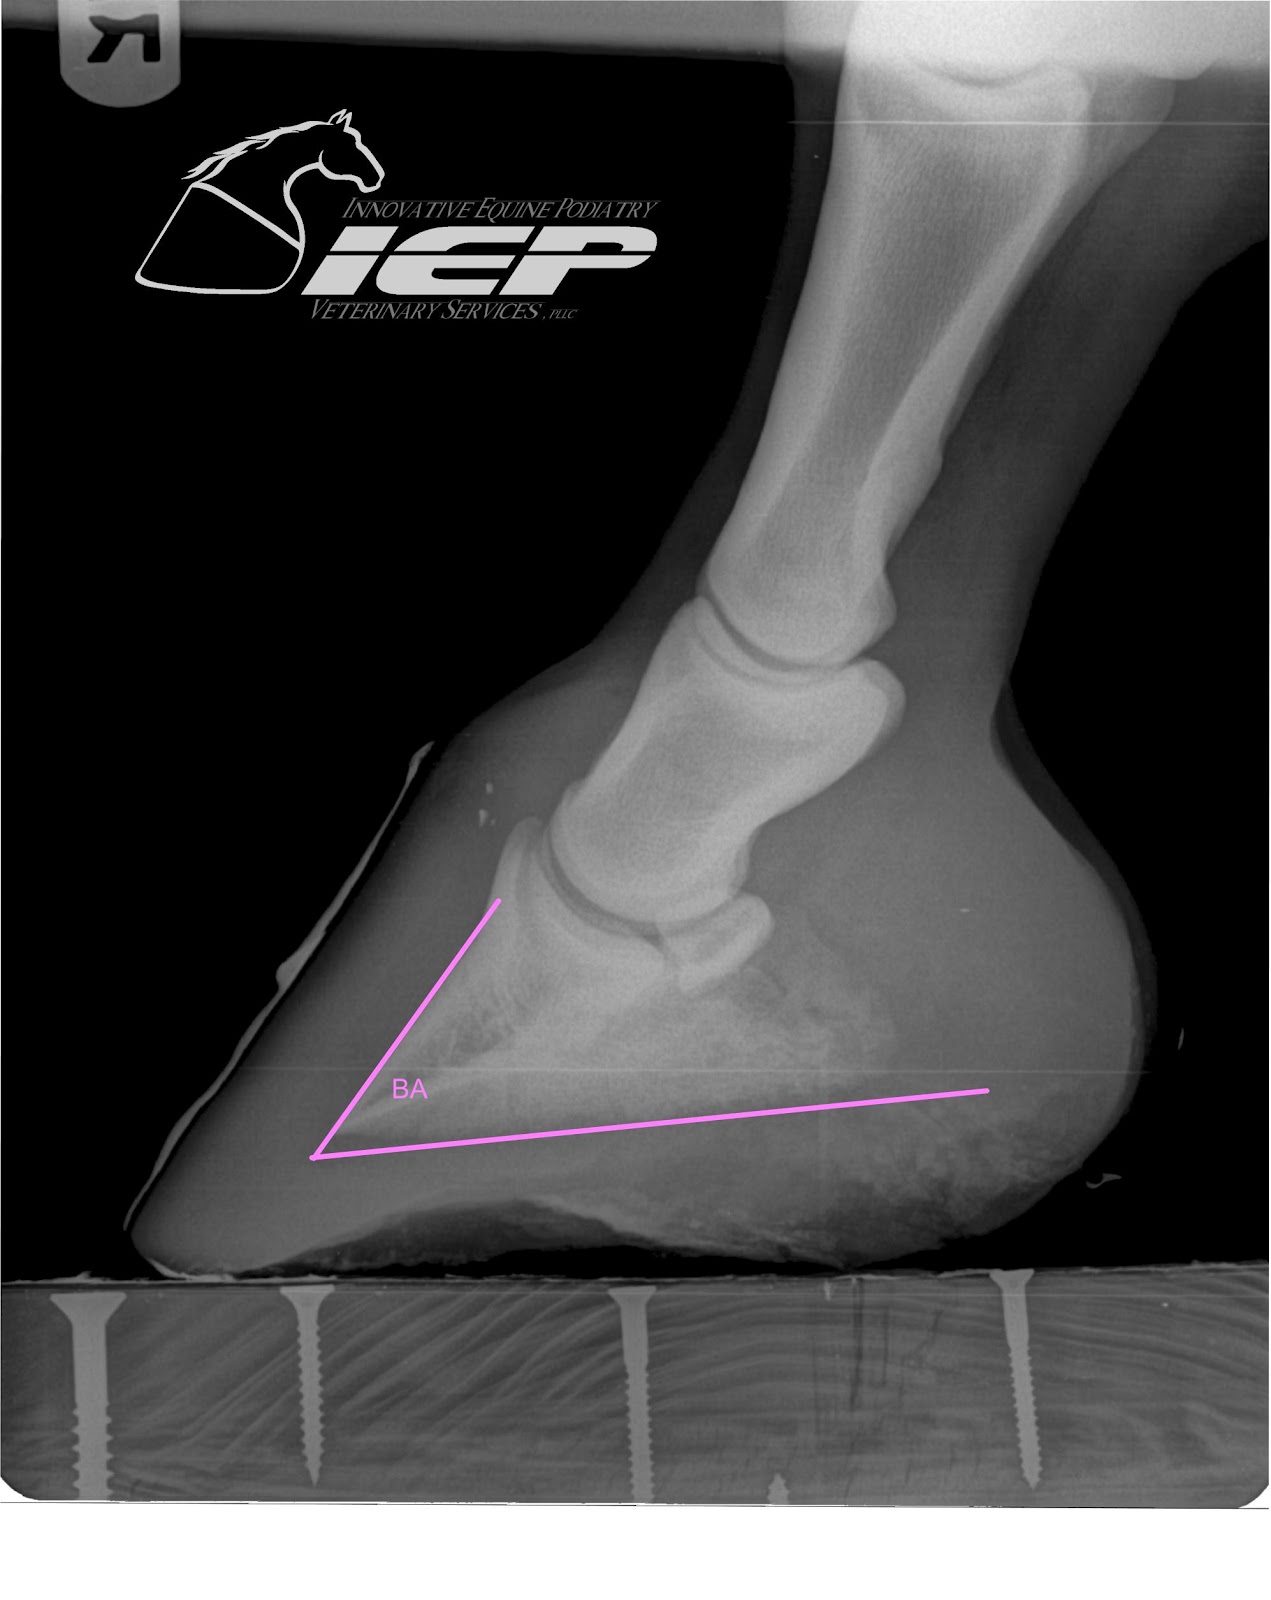

Innovative Equine Podiatry Radiographic parameters measurement guide

Innovative Equine Podiatry Radiographic parameters measurement guide Average Cost Of Horse X Rays Digital radiography has become a standard in equine practice. Your horse may need to be sedated, depending on their. Of course, these advancements come at a cost to the owner. Combined with ultrasound examination, or even ct and. Abvp, founder of south shore equine. Balance equipment, staffing, and overhead expenses to set profitable prices. Radiography is a commonly used imaging. Average Cost Of Horse X Rays.